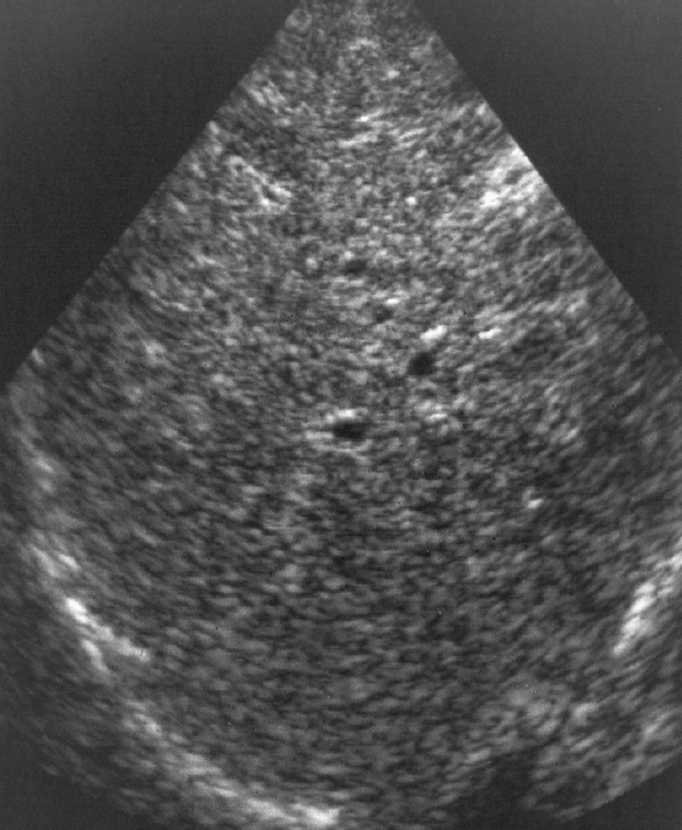

cirrhosis sonographic characteristics

isoechoic regenerative nodules

decreased visualization of vascular structures

fibrosis and altered architecture of cirrhosis cause a

coarse appearance

cirrhosis

enlarged caudate lobe